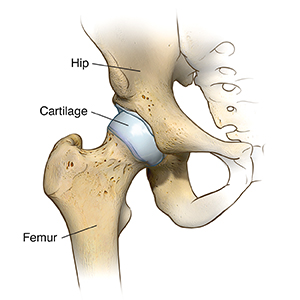

Hip replacement (total hip arthroplasty) is surgery to replace a worn out or damaged hip joint. The surgeon replaces the old joint with an artificial joint (prosthesis). This surgery may be a choice after a hip fracture or for severe pain because of arthritis.

The goal of hip replacement surgery is to replace the parts of the hip joint that have been damaged. It also helps relieve hip pain that can’t be controlled by other treatments.

Osteoarthritis causes loss of joint cartilage in the hip. Damage to the cartilage and bones limits movement and may cause pain. People with severe pain from degenerative joint disease may not be able to do normal activities that involve bending at the hip. These activities include walking and sitting.